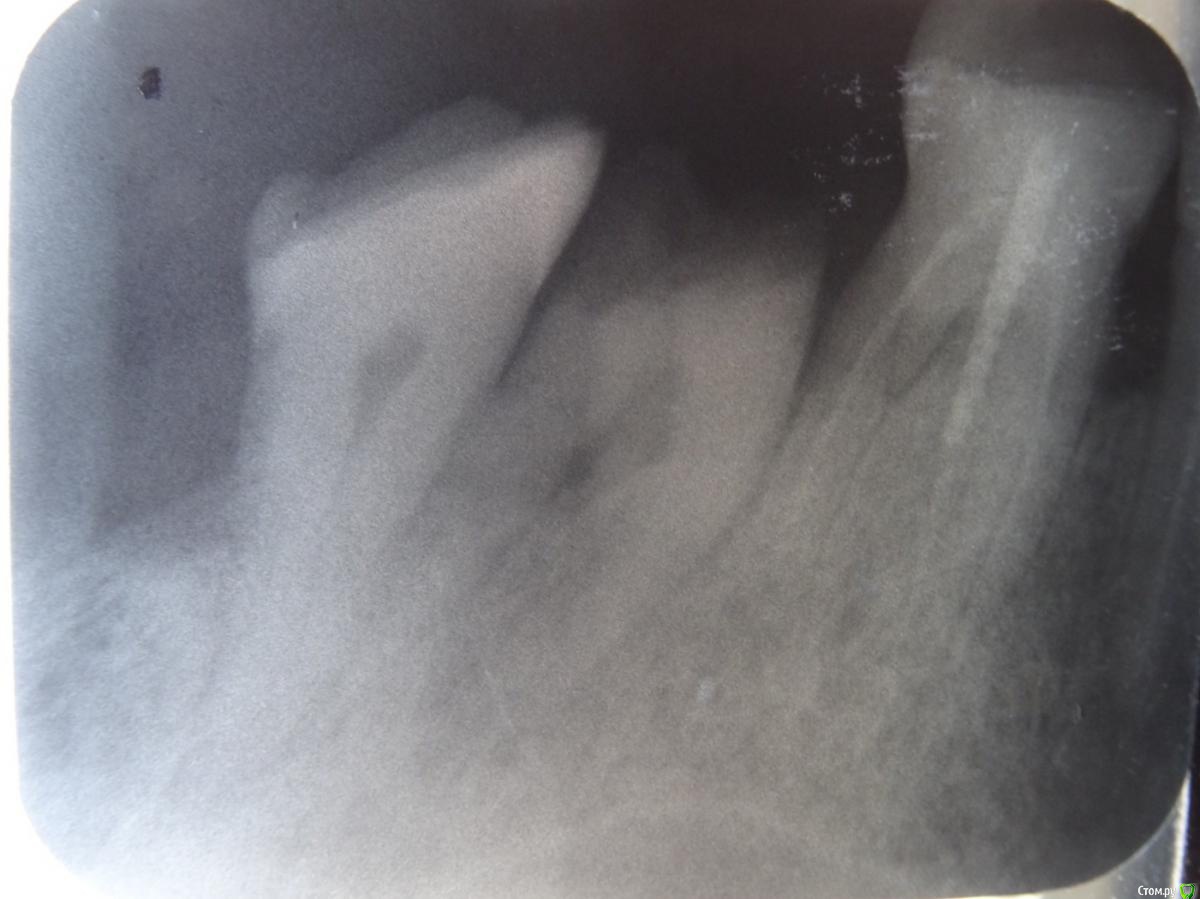

Митя23 Опубликовано 11 марта, 2020 Поделиться Опубликовано 11 марта, 2020 Добрый день!Сломался зуб 7 справа верхний.Есть ли шансы нарастить или однозначно удаление и инплант? Ссылка на комментарий